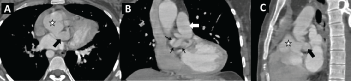

Figure 1: CT angiogram for a patient with pulmonary atresia and ventricular septal defect demonstrating a large, tortuous fistula (small arrows) between the left coronary artery and the pulmonary trunk as the main source of pulmonary blood flow. The aortic root (star) is dilated, the left main coronary artery is severely dilated (black arrow).

Figure 2: Aortic root angiography for a patient with pulmonary atresia and ventricular septal defect (A) A hydrophilic wire was passed from the aortic root across the left coronary artery to the pulmonary trunk, wire course demonstrating the spiral course of the fistula; (B) Aortic root angiogram showing a severely dilated left main coronary artery (white arrow); (C) Schematic showing the cardiac structures of interest.

AO: Ascending Aorta; LCA: Left Coronary Artery; PA: Pulmonary Artery; RCA: Right Coronary Artery.